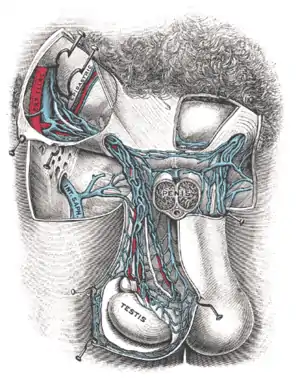

O termo varicocele refere-se especificamente à dilatação e tortuosidade do plexo pampiniforme, que é uma rede de veias que drena o testículo. Este plexo percorre a porção posterior do testículo junto com o epidídimo e o ducto deferente, e então dentro do funículo espermático. Essa rede de veias termina na veia gonadal, ou veia testicular. A veia gonadal direita drena na veia cava inferior, enquanto a veia gonadal esquerda drena na veia renal esquerda, que drena então para a veia cava inferior.

Os pequenos vasos do plexo pampiniforme geralmente variam de 0,5-1,5 mm em diâmetro. A dilatação destes vasos em mais de 2 mm é chamada de varicocele ou varicocelo.